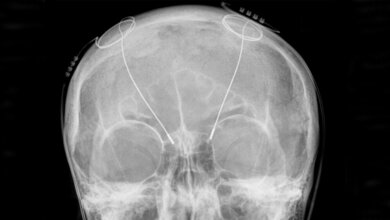

Hoch fokussierter Ultraschall bei Tremor und Parkinson: (v. li.) PD Dr. Claus Christian Pieper, Prof. Hans Schild, Dr. Valeri Borger, Prof. Ulrich Wüllner, Veronika Purrer und Prof. Henning Boecker © Johann Saba/UK Bonn

Essentieller Tremor gehört zu den häufigsten neurologischen Bewegungsstörungen. Er tritt auf, wenn der Betroffene aktiv etwas tut: die Hand zittert bei der Unterschrift, oder wenn ein Glas Wasser zum Mund geführt wird. Ein Mensch, der an Parkinson erkrankt ist, zittert dagegen typischerweise in Ruhe. Bei dem neuen Verfahren schalten fokussierte hochintensive Schallwellen von außen diejenigen Areale im Gehirn ab, die für den essentiellen Tremor oder Tremor bei Parkinson verantwortlich sind. Für die notwendige hochpräzise Lokalisation sorgt die mit Hilfe der Magnetresonanztomographie gesteuerte Neuronavigation, damit nur der gewünschte, etwa zwei Millimeter große Bereich – etwa so breit wie eine Bleistiftmine – in der Tiefe des Gehirns inaktiviert wird. Dazu werden von 1.024 Positionen rund um den Schädel Ultraschallwellen – jede für sich ungefährlich für das Hirngewebe – auf den Zielpunkt gesendet und dort gebündelt. „Nur dort in diesem Schnittpunkt der Wellen wird das Hirngewebe erhitzt und so inaktiviert“, sagt Prof. Dr. Hans Schild, Direktor der Klinik für Radiologie am Universitätsklinikum Bonn. Dazu wird ebenfalls MR kontrolliert die Temperatur am Zielpunkt bis auf etwa 55 bis 60 Grad Celsius gesteigert.